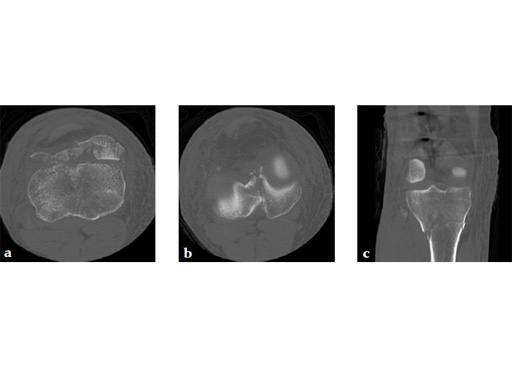

A 36-year-old man sustained a motorcycle injury: right femoral shaft fracture and right hyperextension bicondylar tibial plateau variant (Fig 1, Fig 2).